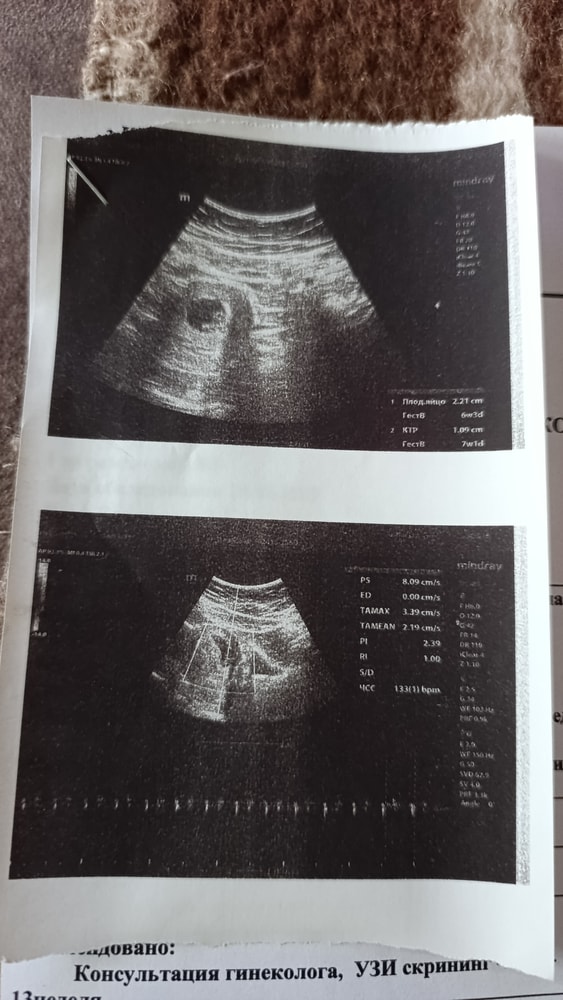

По месячным 9 неделя беременности , на узи сказали что так же 9-10 неделя

Но по мне так это 5-6 неделя, нет? Совсем не видно ребенка

Не похоже на 9-10. Там уже четко было бы всё видно человечка с руками и ногами. Пол на таком сроке невозможно определить даже. Минимум к 12 неделе могут предположить и то это не точно еще. Обычно на втором скрининге пол на 100% видят

делали УЗИ, было 6 недель 6 дней. У вас я думаю что также 6-7 недель в связи с тем, что на 9-10 неделе уже толком всё видно. Возможно врач ошибся. Вам стоит через недельку ещё раз сходить, только в другую клинику, ну и сравнить)☺️